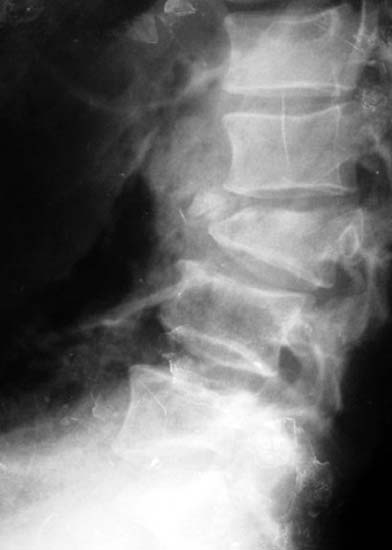

患者男性,30岁,腰3骨折,截瘫

CT显示腰3椎体爆裂,骨块凸入椎管压迫硬膜囊

施行后路椎管前方减压术及经椎弓根固定植骨术,彻底解除 脊髓前方的压迫及后凸畸形,截瘫部分恢复